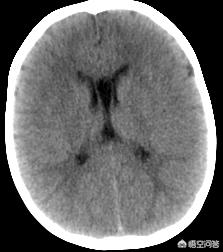

Bien sûr, l'infarctus cérébral ne se résume pas à ces symptômes, mais il s'agit des symptômes les plus typiques et les plus courants. S'il y a de tels symptômes, neuf fois sur dix il s'agit d'un infarctus cérébral (l'autre peut être une ischémie transitoire ou une hémorragie cérébrale), il faut se dépêcher d'aller au service des urgences d'un grand hôpital, le médecin doit vérifier le corps et faire un scanner de la tête qui sera tout à fait clair ! Cela ne retardera pas le meilleur moment pour la thrombolyse, rappelez-vous, le meilleur moment pour la thrombolyse est seulement 4,5-6 heures ah ! (Le temps peut être ajusté dans des circonstances particulières)